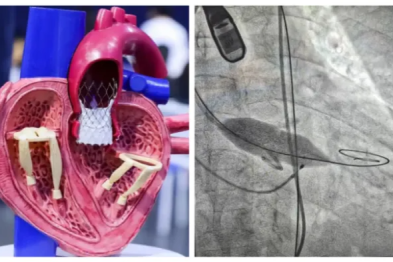

心脏上的「小洞」,竟是脑梗的「后门」